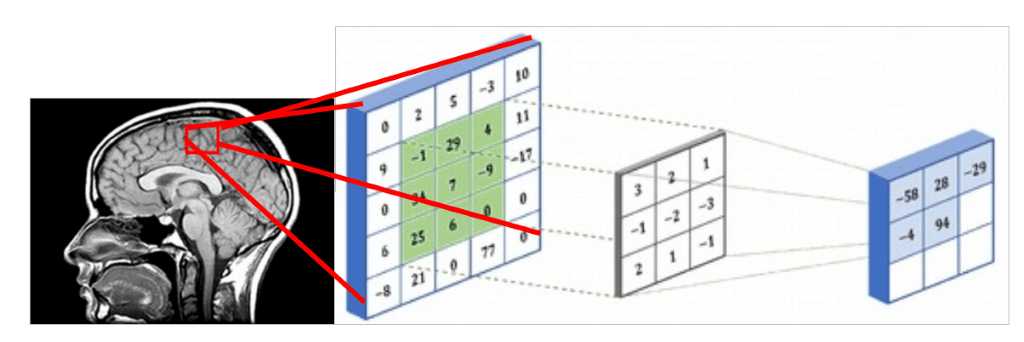

由于医学图像表示 3D 结构,因此处理它们的一种方法是使用 3D 体积的切片并执行常规的 2D 滑动卷积,如下图所示。假设红色矩形是一个 5x5 的图像块,可以用包含强度值的矩阵表示。体 素强度和核用 3x3 卷积核进行卷积,如下图所示。在相同的模式下,内核在整个 2D 网格(医学图像切片)上滑动,并且每次我们执行互相关。卷积的 5x5 补丁的结果存储在 3x3 矩阵中(出于说明目的没有填充),并在网络的下一层传播。